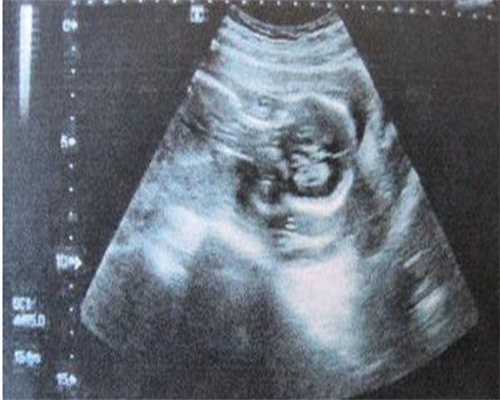

3.手术费用主要是指取卵、胚胎培养费到胚胎移植环节中发生的操作费用,借卵第三代试管婴儿的操作费用在50000元-60000元左右。当然了,这个数据仅供参考,具体依据个人身体状况确认。试管婴儿技能是一种辅佐生殖技能,能够帮助不孕不育患者实现妊娠。其间,借卵第三代试管婴儿技能是由一代、二代试管婴儿技能的基础上拓展而来,其构成胚胎的过程与前两二代无异,仅仅精子和卵子在体外受精构成胚胎后,会在胚胎移植之前,对胚胎进行遗传物质检测,将没有遗传疾病的胚胎挑出来,再移植回子宫,这样就能够防止生出不健康的孩子。